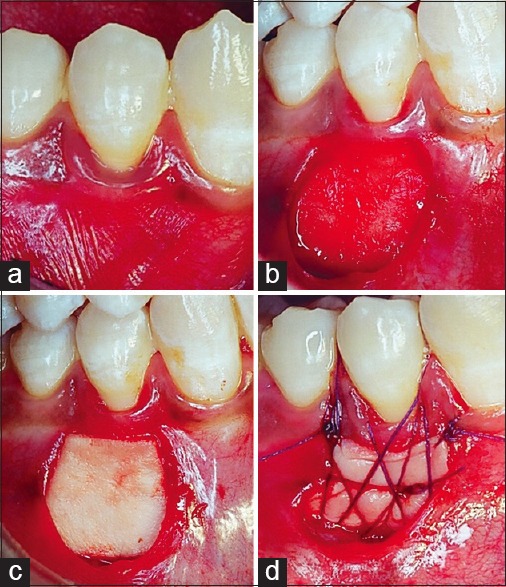

Figure 1.

(a-d) Intraoperative view of free gingival graft procedure

Autogenous free gingival graft

A FGG from the right posterior hard palate was harvested 1 mm apical to the gingival margin of adjacent teeth with a no. 15 scalpel blade. After the donor tissue had been released, the pressure was applied with damp gauze at the donor site. The adipose and glandular tissues on the graft were removed using a scraping motion with a no. 15 scalpel blade. After the donor tissue had been shaped appropriately, it was placed on the recipient bed and fixed with periosteal sutures [Figure 1b–d]. An acrylic palatal stent was placed to cover the wound.